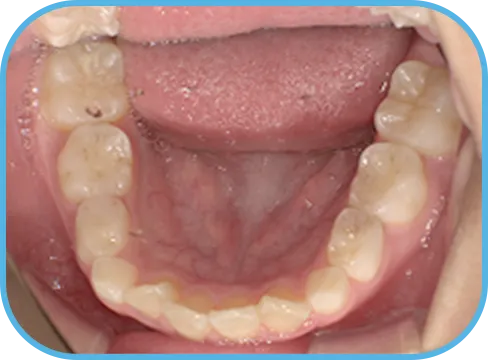

• 下 顎

治療後下顎からの歯の様子